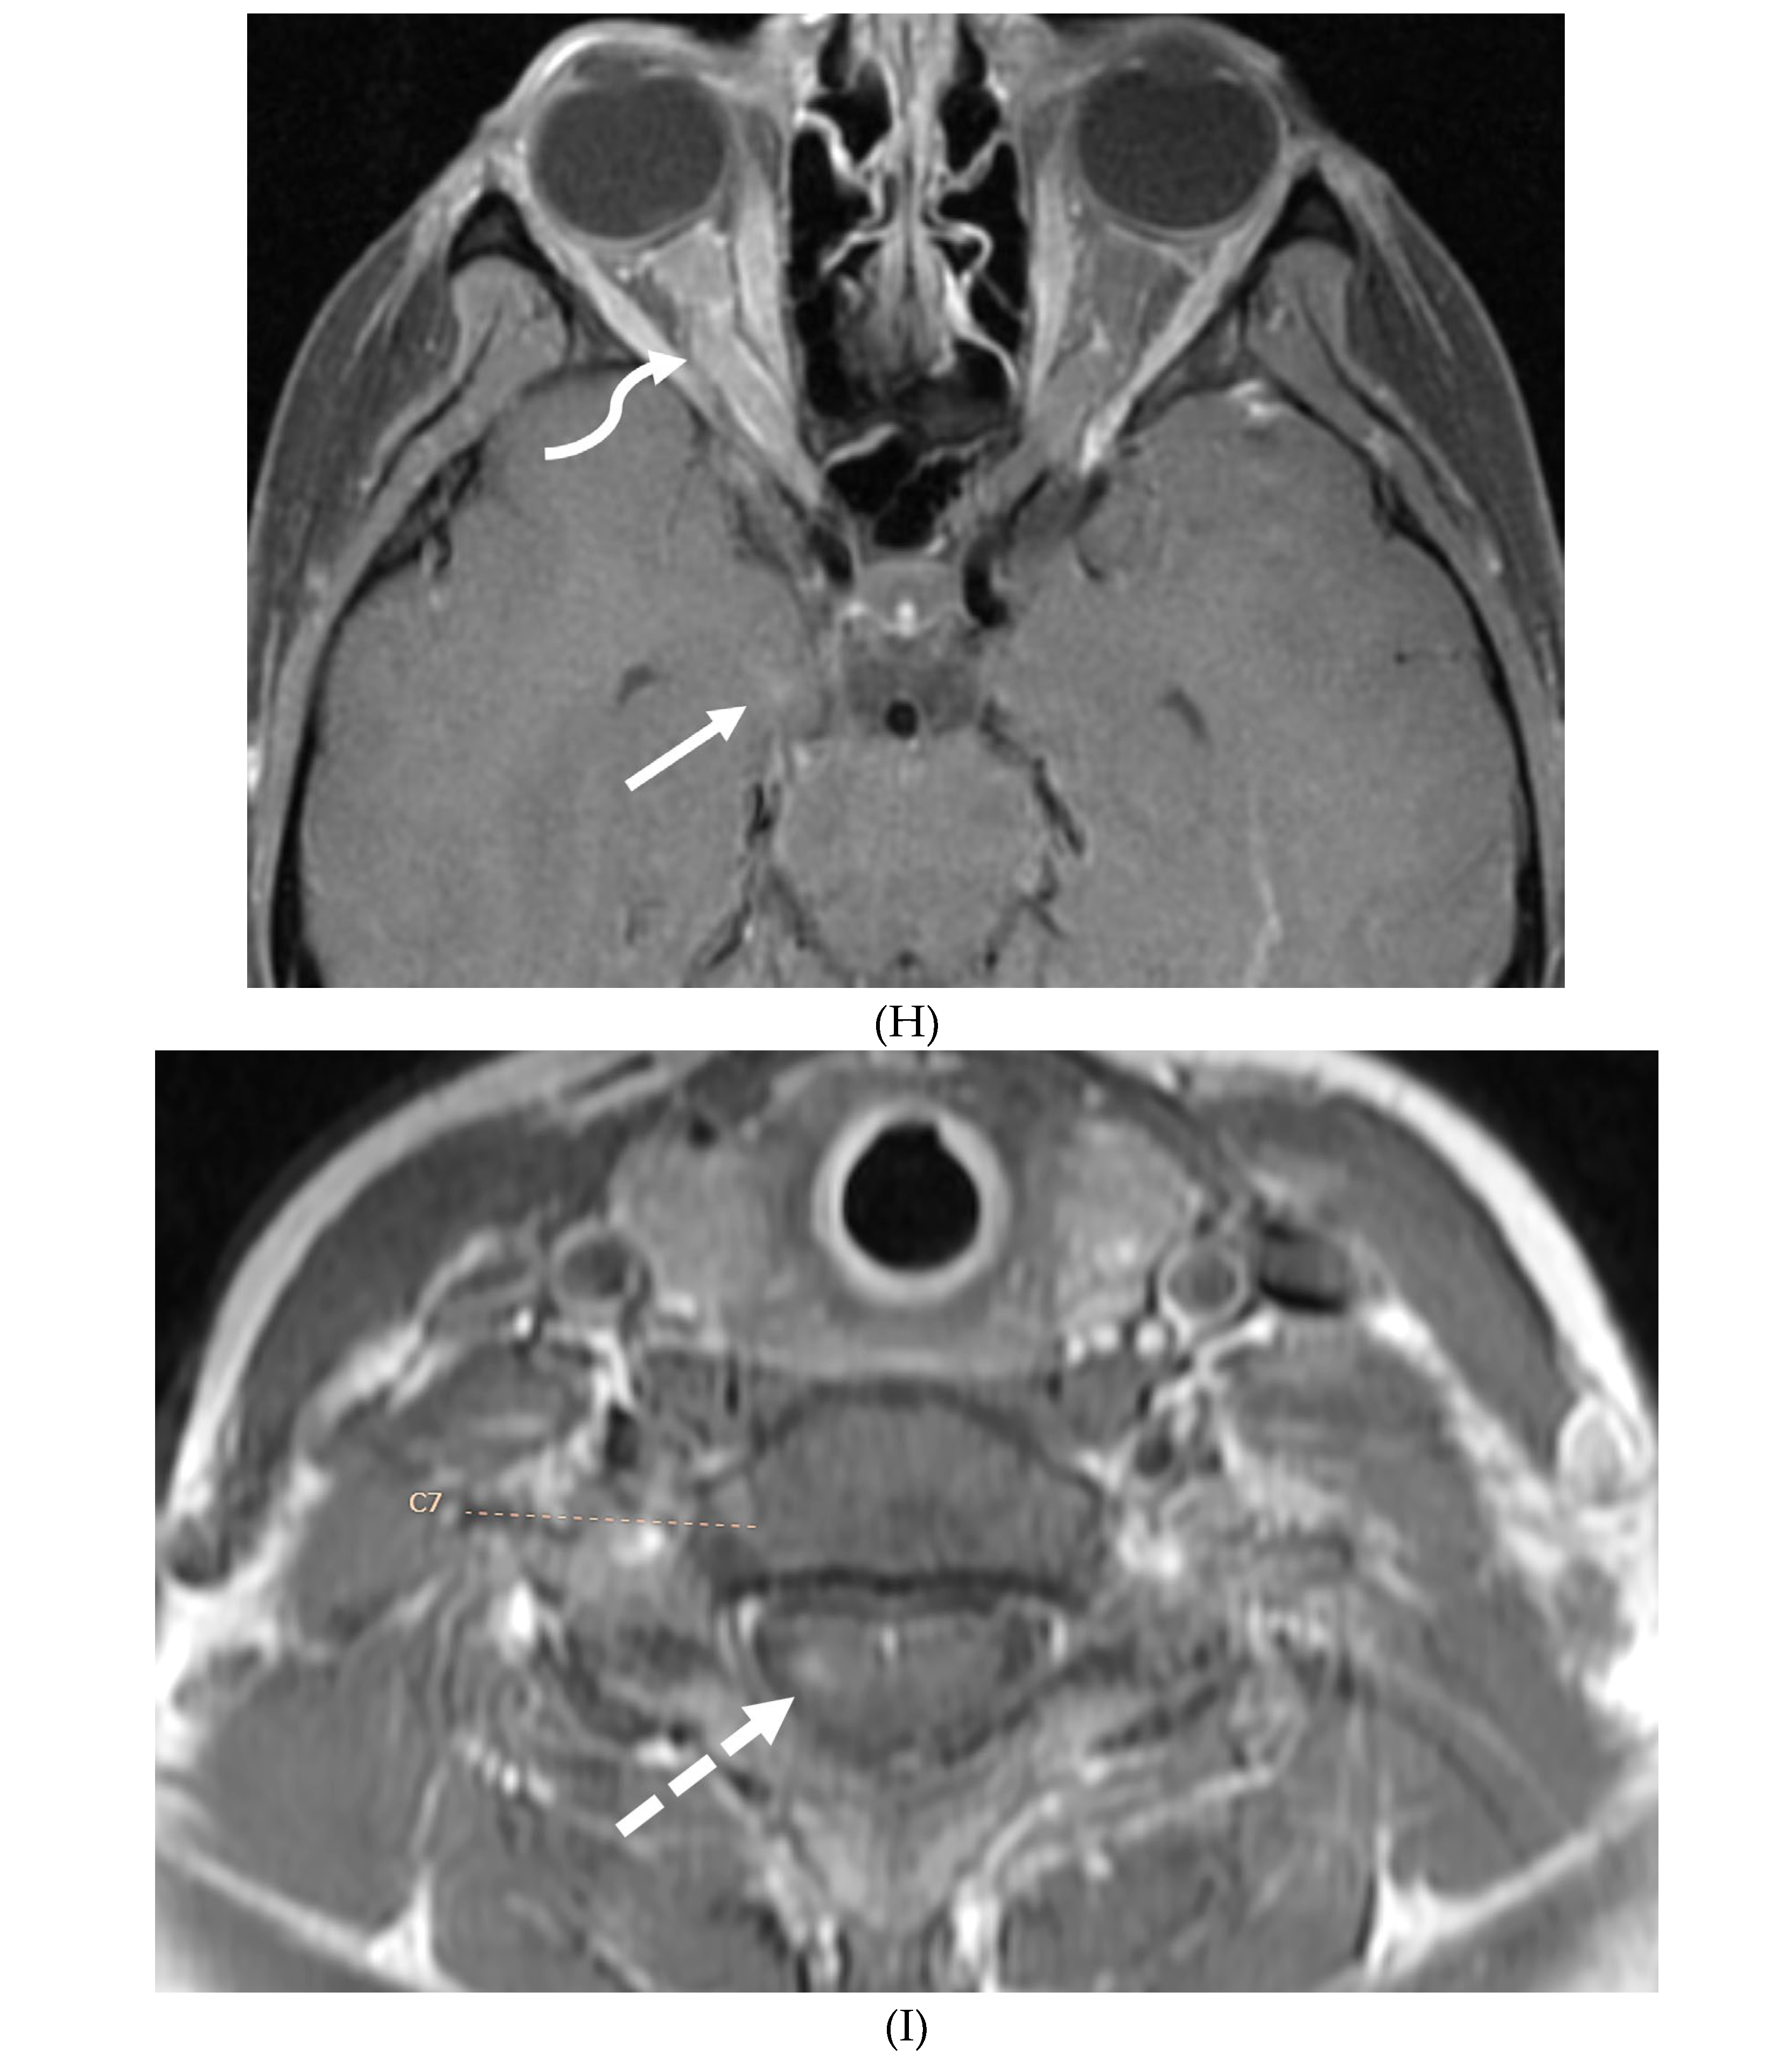

GUILLAIN BARRE SYNDROME

- Chiò A, Cocito D, Leone M, Giordana MT, Mora G, Mutani R; Piemonte and Valle d'Aosta Register for Guillain-Barré Syndrome. Guillain-Barré syndrome: a prospective, population-based incidence and outcome survey. Neurology. 2003 Apr 8;60(7):1146-50. PMID: 12682322. [CrossRef]

- Hughes RA, Rees JH. Clinical and epidemiologic features of Guillain-Barré syndrome. J Infect Dis. 1997 Dec;176 Suppl 2:S92-8. PMID: 9396689. [CrossRef]

- Alter M. The epidemiology of Guillain-Barré syndrome. Ann Neurol. 1990;27 Suppl:S7-12. PMID: 2194431. [CrossRef]

- Alkan O, Yildirim T, Tokmak N, Tan M. Spinal MRI findings of guillain-barré syndrome. J Radiol Case Rep. 2009;3(3):25-8. Epub 2009 Mar 1. PMID: 22470650; PMCID: PMC3303301. [CrossRef]

- Winer JB, Hughes RA, Anderson MJ, Jones DM, Kangro H, Watkins RP. A prospective study of acute idiopathic neuropathy. II. Antecedent events. J Neurol Neurosurg Psychiatry. 1988 May;51(5):613-8. PMID: 3404161; PMCID: PMC1033063. [CrossRef]

- Zuccoli G, Panigrahy A, Bailey A, Fitz C. Redefining the Guillain-Barré spectrum in children: neuroimaging findings of cranial nerve involvement. AJNR Am J Neuroradiol. 2011 Apr;32(4):639-42. Epub 2011 Feb 3. PMID: 21292802; PMCID: PMC7965877. [CrossRef]

- van Doorn PA, Ruts L, Jacobs BC. Clinical features, pathogenesis, and treatment of Guillain-Barré syndrome. Lancet Neurol. 2008 Oct;7(10):939-50. PMID: 18848313. [CrossRef]

- Fulbright RK, Erdum E, Sze G, Byrne T. Cranial nerve enhancement in the Guillain-Barré syndrome. AJNR Am J Neuroradiol. 1995 Apr;16(4 Suppl):923-5. PMID: 7611075; PMCID: PMC8332311.

- Yikilmaz A, Doganay S, Gumus H, Per H, Kumandas S, Coskun A. Magnetic resonance imaging of childhood Guillain-Barre syndrome. Childs Nerv Syst. 2010 Aug;26(8):1103-8. Epub 2010 Jun 17. PMID: 20556395. [CrossRef]

- Byun WM, Park WK, Park BH, Ahn SH, Hwang MS, Chang JC. Guillain-Barré syndrome: MR imaging findings of the spine in eight patients. Radiology. 1998 Jul;208(1):137-41. PMID: 9646804. [CrossRef]

- Malhotra A, Zhang M, Wu X, Jindal S, Durand D, Makhani N. MRI findings of optic pathway involvement in Miller Fisher syndrome in 3 pediatric patients and a review of the literature. J Clin Neurosci. 2017 May;39:63-67. Epub 2017 Feb 10. PMID: 28209311. [CrossRef]

- Gallardo E, Sedano MJ, Orizaola P, Sánchez-Juan P, González-Suárez A, García A, Terán-Villagrá N, Ruiz-Soto M, Álvaro RL, Berciano MT, Lafarga M, Berciano J. Spinal nerve involvement in early Guillain-Barré syndrome: a clinico-electrophysiological, ultrasonographic and pathological study. Clin Neurophysiol. 2015 Apr;126(4):810-9. Epub 2014 Aug 21. PMID: 25213352. [CrossRef]

- Razali SNO, Arumugam T, Yuki N, Rozalli FI, Goh KJ, Shahrizaila N. Serial peripheral nerve ultrasound in Guillain-Barré syndrome. Clin Neurophysiol. 2016 Feb;127(2):1652-1656. Epub 2015 Jul 17. PMID: 26228791. [CrossRef]